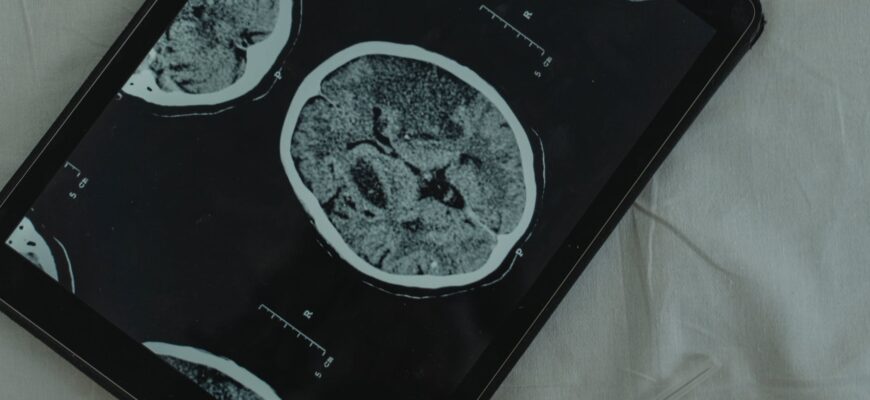

Creierul este un computer extraordinar cu 86 de miliarde de neuroni și 85 de miliarde de celule non-neurale. Neuronii sunt unitatea fundamentală a sistemului nervos, care controlează tot ceea ce facem: respirăm, mergem, simțim și gândim.

Există numeroase studii privind efectele zahărului asupra creierului. Unele dintre cele mai mari companii folosesc acum scanări ale creierului pentru a studia modul în care reacționăm neurologic la anumite alimente, în special zahăr. Ei au descoperit că creierul se luminează la zahăr la fel cum o face la substanțele interzise.